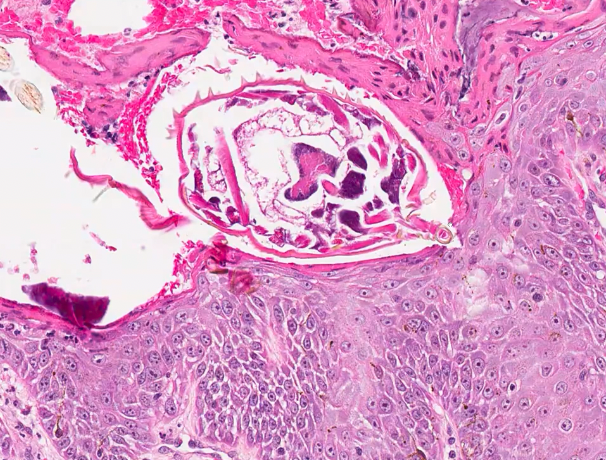

skin scrapings on Scruffy are negative for mites (sarcoptes and demodex). Impression smear reveals neutrophils and rounded keratinocytes. You decide to perform a skin biopsy and bacterial culture and sensitivity from a similar pustule. What dermpath pattern is evident at low mag?

c. epidermal pustular

epidermal pustular

9 that is located in slot 4.

What cells are evident at higher mag?

animal with pustule and epidermal pustular

neutrophils, eosinophils, acantholytic keratinocytes

what is your diagnosis animal with pustule with neutrophils, eosinophils, acantholytic keratinocytes

no bacteria

pemphigus foliaceus